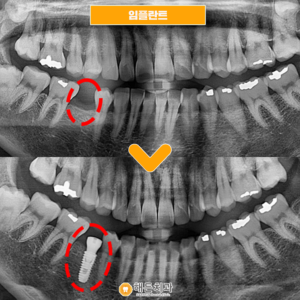

천안아산치과 현명한 결정을 해요 (치료기간 : 2022년 7월 ~ 22년 9월)   안녕하세요. 오늘은 저희 천안아산치과 해든의 임플란트를 추천 받아 내원하여 임플란트 시술하신 환자분을 소개해 드릴까 하는데요. 아래 사진을 보면서 설명해 드리도록 하겠습니다.   위 사진은 천안아산치과 해든치과에 내원하신 김*지님의 치아 사진입니다. 김*지님은 하악 오른쪽 부분 빨간색 표시한 부분, 작은 더보기…